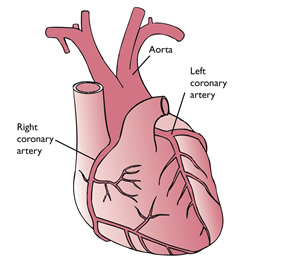

Blood Supply

Arterial supply

The heart gets its oxygen and nutrients from 2 arteries-the right and left coronary arteries, which are the first branches of aorta.

The right coronary artery[RCA]

It occurs from the right aortic sinus and descends in the coronary sulcus between the right auricle and right ventricle. It then passes towards the inferior border of the heart, where it gives off a marginal branch that runs towards the apex. After giving off this branch, the RCA turns to the left and enters the posterior interventricular groove, where it gives off its largest branch, the posterior interventricular branch. This branch supplies both ventricles runs towards the apex and anastomoses with the anterior interventricular branch of the left coronary artery.

The left coronary artery[LCA]

It arises from the left aortic sinus; passes between the left auricle and pulmonary trunk to reach the coronary groove. It soon divides into two terminal branches[1], The anterior interventricular branch and[1]the circumflex branch.

The anterior interventricular branch passes along the anterior interventricular groove to the apex of the heart; It anastomoses with the right coronary artery’s posterior interventricular branch.